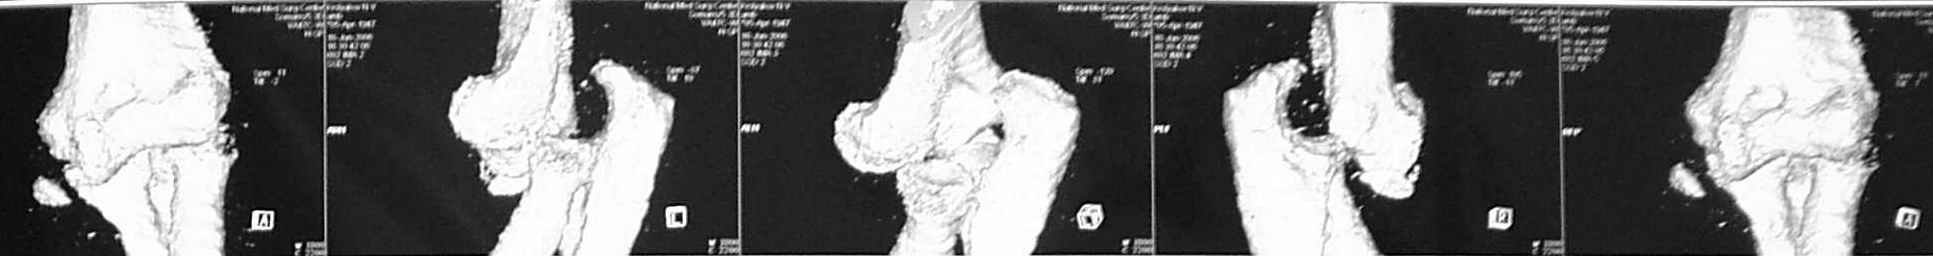

3 недели лечился в травмпункте с диагнозом отрывной перелом медиального надмыщелка левой плечевой кости (Rtg-1). Лечение состояло в ношении руки на косыночной повязке. Затем в другом учреждении сделали КТ (рис 2,3,4).

На R-граммах имеется отрывной перелом внутреннего мыщелка плечевой кости (суставной поверхности). Взаимоотношения в суставе правильные. На КТ - задний вывих предплечья. А не вправляли ли в травмпункте предплечье, не наложив затем гипсовой иммобилизации??? Чтобы предплечье вывихнулось в косынке - ... я не встречал... По тактике - оперативное лечение и чем быстрее, тел лучше. Время идет сейчас не на пользу. Идти задним доступом либо с остеотомией локтевого отростка, либо с V-образным рассечением сухожилия трицепса. Костный свободный фрагмент желательно удалить.

Удивлен такими различиями между КТ и Rtg... никогда с таким не встречался. а рентген-снимках никакого намека на вывих не вижу, поэтому и обвинять в халатности персонал травмпункта не стоит. Хотя вполне вероятно, что пальпаторно можно было заподозрить несоответствие обследования с реальной картиной.

Чудеса конечно бывают, но не настолько же? Если рентгенограммы и томограммы одной конечности, то они явно разнесены по времени и событьиям. Нужно что-то повторить Rg или КТ и тогда уже думать. С уважением Шевырев К.В., МОНИКИ